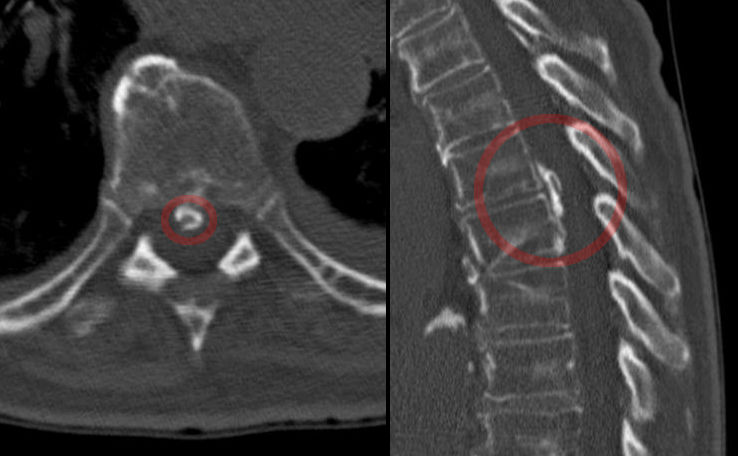

Your medical professional might also advise a collection of imaging procedures to establish the source of your pain in the back. These imaging procedures can include x-rays, bone scans, as well as CT scans. These imaging treatments can be handy, but they aren't always needed for the majority of instances of pain in the back. If you have severe neck and back pain, your physician may advise an injection. These injections can aid to eliminate pain and also decrease swelling.

3. Diagnosis of Back Pain

If you have a pinched nerve in lower back, your medical professional will certainly perform a physical examination to figure out the cause. If your doctor is unclear of the reason, he or she might buy imaging tests. These examinations can discover nerve root compression as well as aid to figure out the degree of the damage. You can additionally have spine shots to relieve the discomfort and swelling. Your doctor might additionally recommend you dental or infused corticosteroids if your other treatments have actually not worked. If you have diabetics issues, you go to greater threat for creating nerve compression. You ought to prevent repeated tasks that stress your back and also ought to additionally add toughness workouts to your regular exercise regimen.